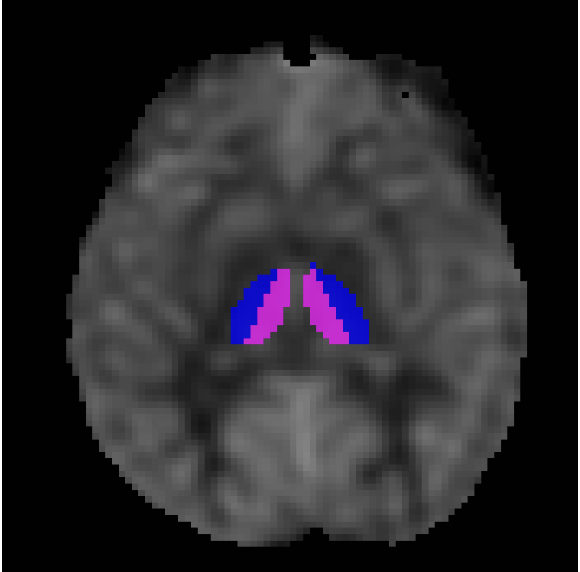

Thalamic Blood Flow in Self-Limited Epilepsy with Centrotemporal Spikes

by Niki Iasinovschi

๐Ÿ… Recipient of the 2024 Barbara and Sandy Dornbusch Award

Investigating the role of the thalamus in a common type of childhood epilepsy using MRI to measure blood flow to the thalamus in children of various ages with and without epilepsy.